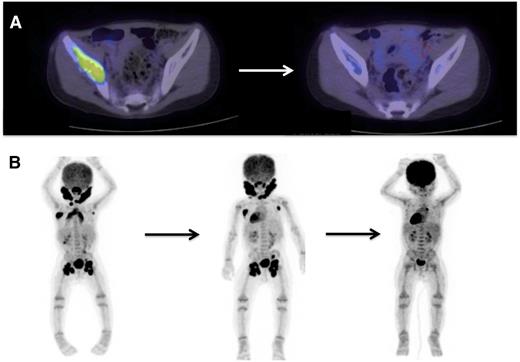

PET scan is effective in evaluating response to treatment of most lesions (Figure 4) except vertebral lesions, which may be better visualized by MRI that will capture changes in soft tissue or enhancement of the bone.28 Vertebral CT scans may add information on bone response to therapy and CT scans are also optimal for following bony lesions of the skull, whereas MRI is most effective for parenchymal brain and pituitary lesions. Bone healing may lag resolution of other lesions (Figures 5-6). CT scanning is also an optimal study to evaluate lung lesions, though cysts may remain as permanent consequences following resolution of nodular parenchymal lung lesions (Figure 7). Clinical examination is sufficient follow-up for proven skin-limited disease, and patients with single bone lesions may be followed by clinical examination, radiograph, or MRI to minimize radiation exposure.

PET/CT scans are effective to stage disease and to evaluate response to therapy in LCH. Examples of 18-fluoro-deoxyglucose–PET scans with CT identifying response to therapy. (A) A patient with multifocal bone disease with interval improvement of pelvic lesion and decreased PET avidity. (B) A patient with multifocal lymph node disease (cervical, axillary, inguinal) who initially failed to respond to cytarabine therapy, then had significant response to 2 cycles of clofarabine.